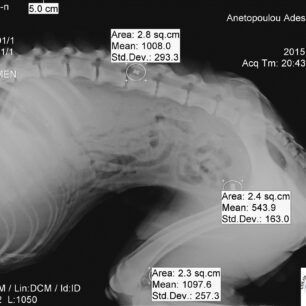

Το ζώο ήταν τόσο εξασθενημένο, τόσο υποσιτισμένο και αφυδατωμένο που σε κάθε δύο βήματα έπεφτε. Σηκωνότανε με δυσκολία ενώ από την μύτη του έσταζε αίμα. Τελικά η κοπέλα με τη βοήθεια ενός ακόμα ευαίσθητου νεαρού του κτηνιάτρου Φιλήμονα Διαμαντή κατάφερε να το πιάσει. Το σκυλί μεταφέρθηκε στο κτηνιατρείο του κ. Διαμαντή και οι ακτινογραφίες έδειξαν ότι στο κορμί του έφερε και τρία σφαιρίδια από αεροβόλο όπλο.

Το εκπληκτικότερο όμως, που είναι και ο λόγος για τον οποίο γράφω αυτό το άρθρο, είναι ότι στις ακτινογραφίες που του έγιναν με έκπληξη είδαμε να φαίνονται οι σκιές από τρία μικρά βόλια αεροβόλου όπλου σε διάφορα σημεία του σώματος του.